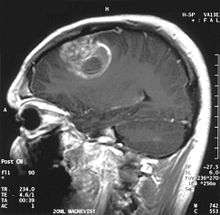

| Coronal MRI with contrast of a glioblastoma WHO grade IV in a 15-year-old male | |

When viewed with MRI, glioblastomas often appear as ring-enhancing lesions. The appearance is not specific, however, as other lesions such as abscess, metastasis, tumefactive multiple sclerosis, and other entities may have a similar appearance.[43] Definitive diagnosis of a suspected GBM on CT or MRI requires a stereotactic biopsy or a craniotomy with tumor resection and pathologic confirmation. Because the tumor grade is based upon the most malignant portion of the tumor, biopsy or subtotal tumor resection can result in undergrading of the lesion. Imaging of tumor blood flow using perfusion MRI and measuring tumor metabolite concentration with MR spectroscopy may add value to standard MRI in select cases by showing increased relative cerebral blood volume and increased choline peak respectively, but pathology remains the gold standard for diagnosis and molecular characterization.